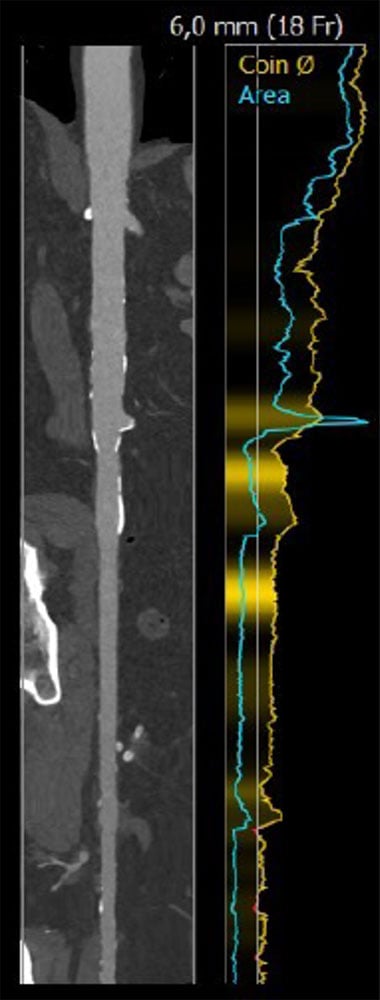

Fallplanung: CT

Anulus: 29,6 cm

LVOT: 32,2 cm

Mäßige Ca2+, Trikuspid

LAO 3° - kranial 19°

RAO 14° - kaudal 9°